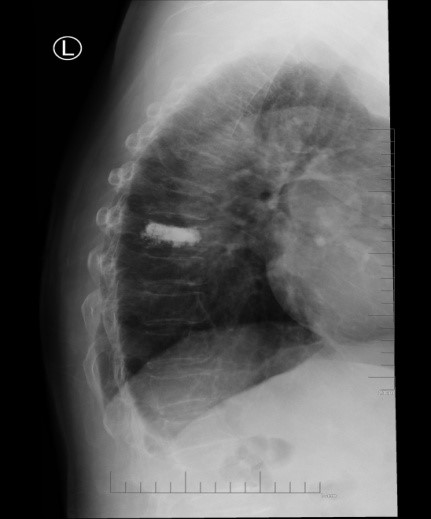

吴老太太今年86岁,同时患有心脏病、老慢支、哮喘、糖尿病等多种疾病,不久前因为并发心衰、呼衰在独墅湖医院经抢救后脱离危险。然而不巧的是,几天前自己在家只轻轻扭了一下腰,就感觉背部疼痛难忍,寝食难安。于是来到我院骨科就诊,医生怀疑是脊柱骨质疏松性骨折,安排收治住院,对病患进行磁共振检查后证实是“第8胸椎压缩性骨折”。

医生在诊断后决定行经皮椎体后突成形术(简称PKP术),需要病人在全身麻醉下俯卧位,医生在全程透视下完成手术。对于一般的患者来说不成问题,而对吴老太太而言却难以实施。首先,她的全身情况较差,心肺功能不全,基础疾病多且严重。入院时就有明显的呼吸困难,氧饱和度只有70%左右,很难耐受全身麻醉。即使勉强度过手术阶段,术后也可能要气管插管,靠呼吸机维持生命,肺部感染则难以控制。其次,如果采用局部麻醉俯卧位手术,尽管可以规避全麻的风险,但该患者根本不能承受俯卧位对心肺功能的影响。但如果不采取手术,卧床以及日夜不停的疼痛对已经遭受过心衰和呼衰的吴老太太来说是雪上加霜。